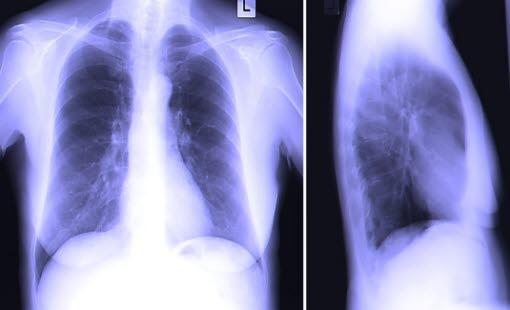

Pneumokokker er en type bakterier som kan forårsake lungebetennelse og blodforgiftning, særlig hos eldre og andre med redusert helsetilstand. Formålet med en vaksine mot pneumokokker er at den skal forebygge slike livstruende infeksjoner.